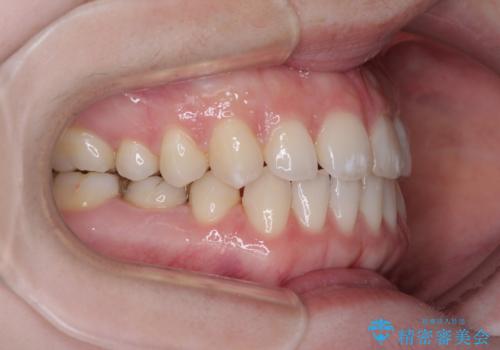

すきっ歯をインビザラインできれいな歯並びに改善

- 前歯の隙間を気にして来院された患者様です。

隙間や叢生の程度はそれほど著しいものではなかったので、インビザラインでもワイヤー矯正でも対応可能でしたが、極力目立たない装置を希望されたため、インビザラインにて矯正治療を行うこととしました。